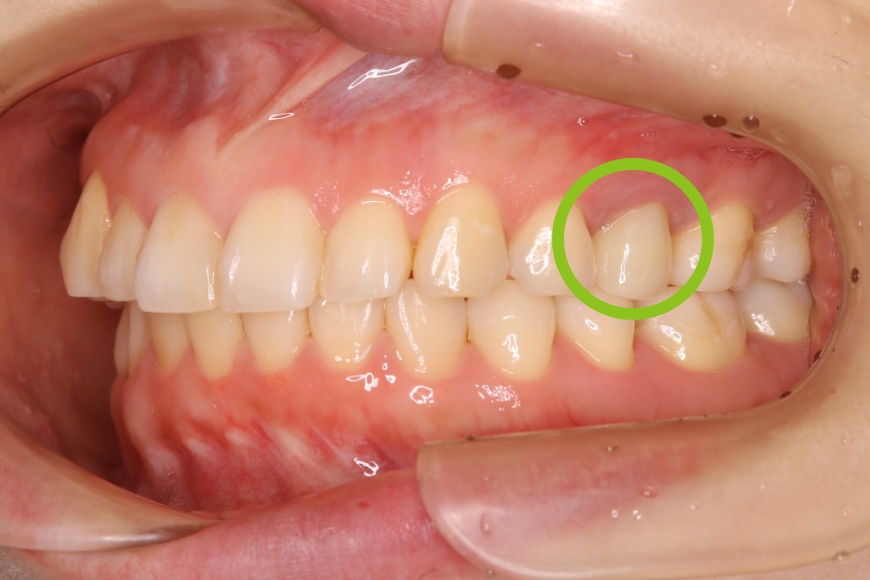

20代女性 上の奥歯へのジルコニア治療およびメタルタトゥーの除去

治療前①

治療後①

治療前②

治療後②

治療内容 奥歯の被せものをやり直したい、また、歯ぐきが黒くて気になるとのことで来院されました。

金属の被せの表面にプラスチックが張り付けてあり、また、使用している金属が溶け出し、歯ぐきが黒くなっていました(メタルタトゥー)。

装着してある全ての金属を除去後、歯ぐきのメタルタトゥーにレーザー照射を行い、健康なピンク色の歯ぐきを回復しました。その後、審美的および耐久性に優れるジルコニアの被せものを装着しました。

治療後は金属アレルギーのリスクがゼロとなり、メタルタトゥーが起こる心配もありません。

治療期間・回数 治療期間:約3ヶ月程度

通院回数:5回程度

治療費用(総額)

132,000

( ジルコニア 110,000円、メタルタトゥー除去1か所 22,000円。時期や手法により異なる場合があります。)

副作用・リスク ・ジルコニアは、保険治療のプラスチックに比べ硬く耐久性がありますが、強い力が加わるとごくまれに割れたり欠けたりすることがあります。

・メタルタトゥー除去後は、一時的な出血・腫脹・疼痛が生じる場合がまれにあります。

・喫煙や他の色素沈着因子により、再発の可能性があります。